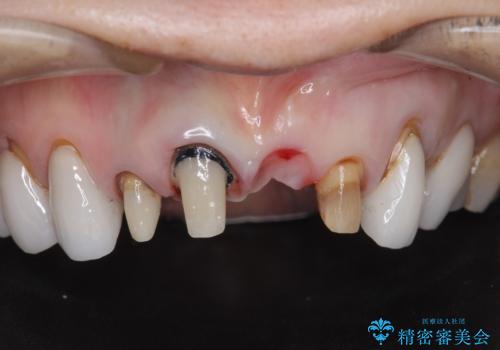

[ セラミック治療 ] 歯ぐきの際の黒ずみを改善したい

- 歯ぐきとセラミックの間の黒ずみが目立つので、きれいに治してほしい。と希望され来院されました。

歯ぐきの位置が変化しクラウン下の歯が見えるようになってしまったことで、審美障害が生じている状態です。

クラウンマージンの再設定を行うことで、黒ずんだ部分を再度覆い、審美障害を改善します。

- 52.8万円(ジルコニアクラウン×4・仮歯×4)費用は治療当時の料金となります